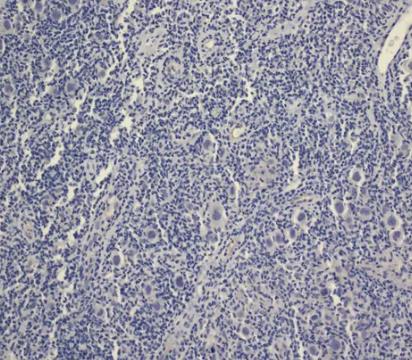

3. 碳酸聚酯膜冲洗、固定、HE染色,镜下阅片观察趋化人组织细胞淋巴瘤细胞(U937)数量;

4. 血球计数板计数趋化细胞离心浓缩液中人组织细胞淋巴瘤细胞(U937)数量,检测单核细胞趋化蛋白-1(MCP-1)趋化人组织细胞淋巴瘤细胞(U937)的能力;

[结果]1.单核细胞趋化蛋白-1(MCP-1)对人组织细胞淋巴瘤细胞(U937)的趋化作用高于空白对照组,有显著性差异,差异有统计学意义(P<0.05);2.单核细胞趋化蛋白-1(MCP-1)的趋化能力和浓度相关,随着浓度增加,对人组织细胞淋巴瘤细胞(U937)的趋化作用越明显(P<0.05)。

[结论]单核细胞趋化蛋白-1(MCP-1)对人组织细胞淋巴瘤细胞(U937)具有趋化作用,不同浓度单核细胞趋化蛋白-1(MCP-1)对人组织细胞淋巴瘤细胞(U937)趋化活性存在差异,单核细胞趋化蛋白-1(MCP-1)浓度越大,对人组织细胞淋巴瘤细胞(U937)的促迁移作用越明显。